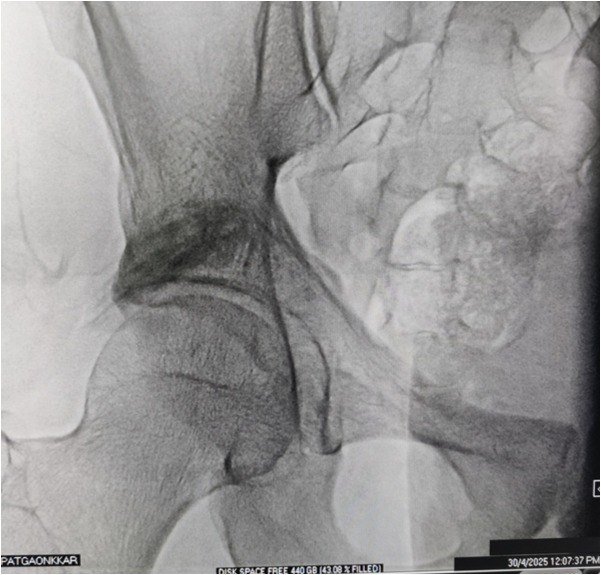

• Imaging-guided targeting: Fluoroscopy or ultrasound helps the doctor visualize the exact structure causing pain.

• Precise treatment delivery: Medication to reduce inflammation,Heat energy for nerve ablation (RFA), Electrical stimulation (nerve modulation)